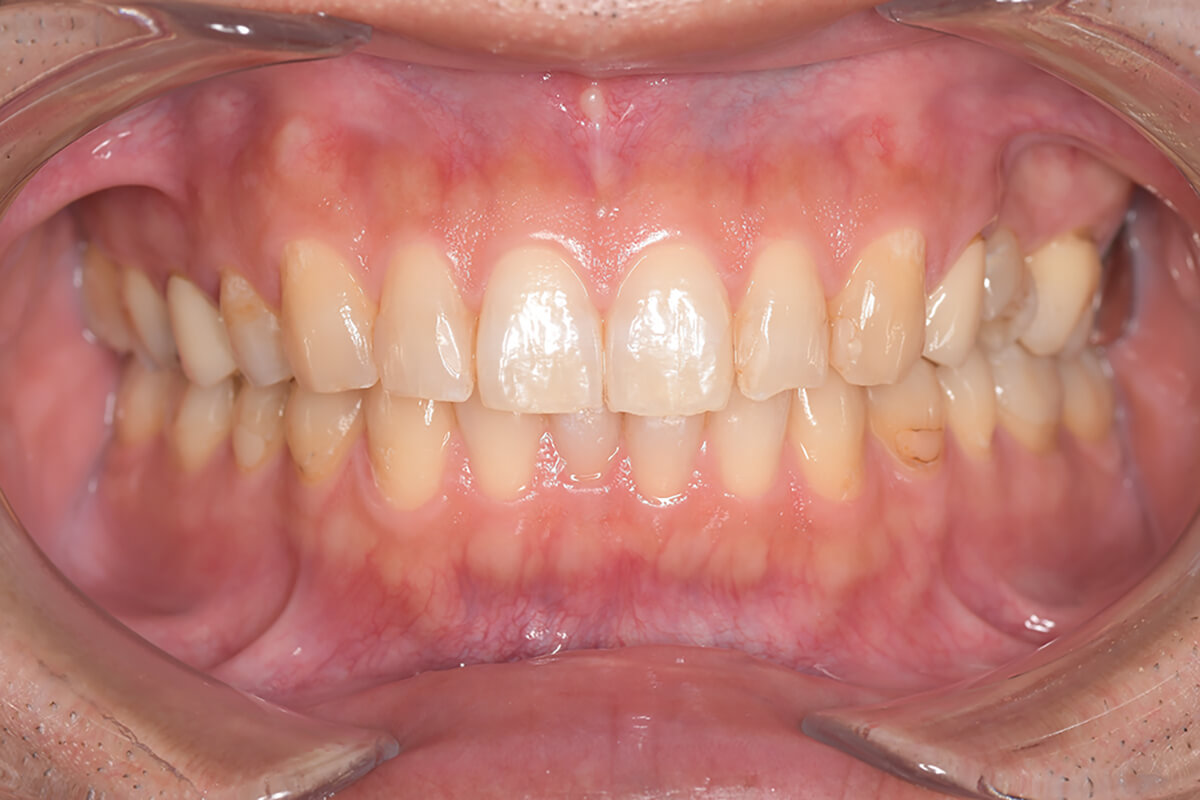

Before

| 主訴 | 見た目をきれいにしたい |

|---|---|

| 治療期間 | 6ヶ月 |

| 治療費 | ジルコニアボンド(セラミックの被せもの)¥165,000×7(税込み) オフィスホワイトニング4回 ¥4,400×4(税込み) ホームホワイトニング¥11,000 |

| リスク・副作用 | かみ合わせがとても強い方の場合、稀に割れてしまうことがあります。 |

| 先生からの提案 | 上の前歯6本と右下の2番目の歯はセラミックの被せもので治療。 残りの下の前歯5本はプラスチックの材料で虫歯を治療し、 ホワイトニングをおこないました。白くなったご自身の歯の色に合わせてセラミックの 被せものを作成しています。 模型上で完成後をシュミレーションし、上の歯茎の位置をきれいに見えるように 揃えています。(外科処置はしていません) |